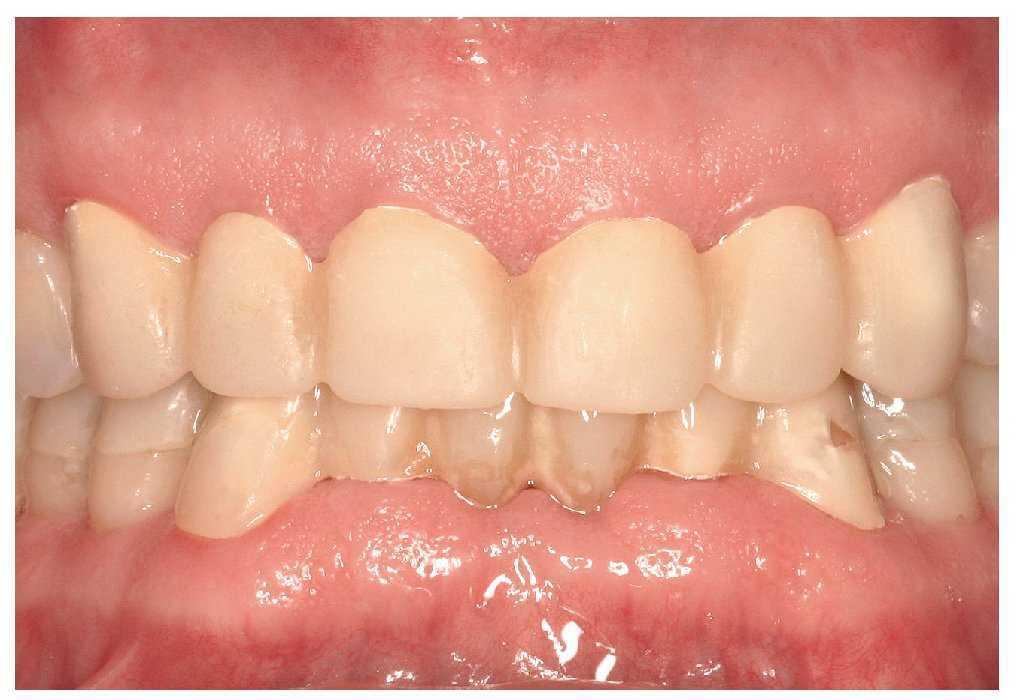

La primera revisión se realizó a los tres días de la colocación (figs. 23 y 24) y las siguientes tuvieron lugar al cabo de una, dos y cuatro semanas. Se estableció una frecuencia trimestral de las visitas de revisión. Además de controlar la oclusión, la función y la férula inferior se realizaron reevaluaciones periódicas de la situación periodontal. Con la adopción de otras medidas de tratamiento periodontal inicial a los tres y a los nueve meses en el maxilar y en la mandíbula fue posible disminuir de forma duradera las profundidades de sondaje.

Figura 24. Rehabilitación terminada sin restauraciones de metal visibles.